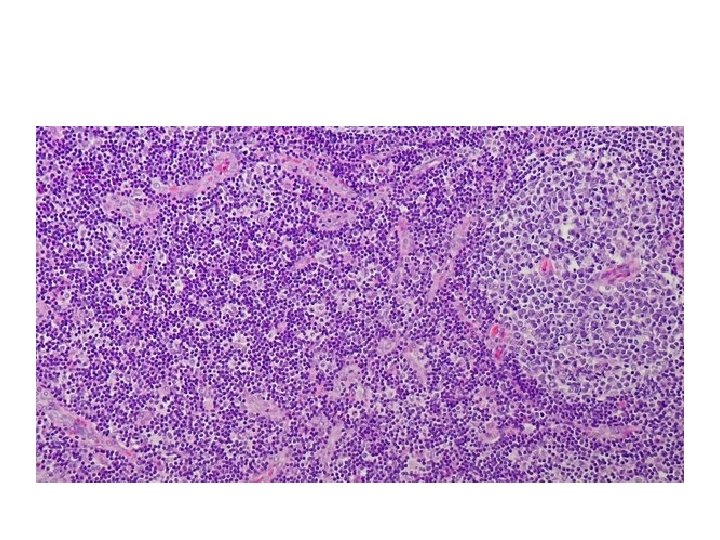

Follicular hyperplasia

• No neutrophils • Can be confused with follicular lymphoma (1) the preservation of the lymph node architecture; (2) variation in the shape and size of the germinal centers; (3) the presence of a mixture of germinal center lymphocytes of varying shape and size; (4) prominent phagocytic and mitotic activity in germinal centers. (5) BCL 2 is negative in the follicles and positive in follicular lymphoma